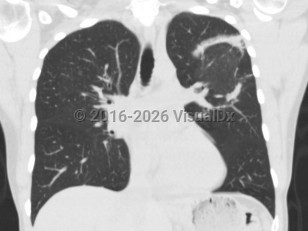

Cryptogenic organizing pneumoniaCryptogenic organizing pneumonia